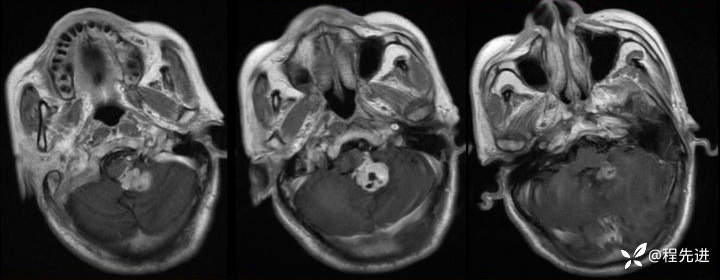

T1:

img